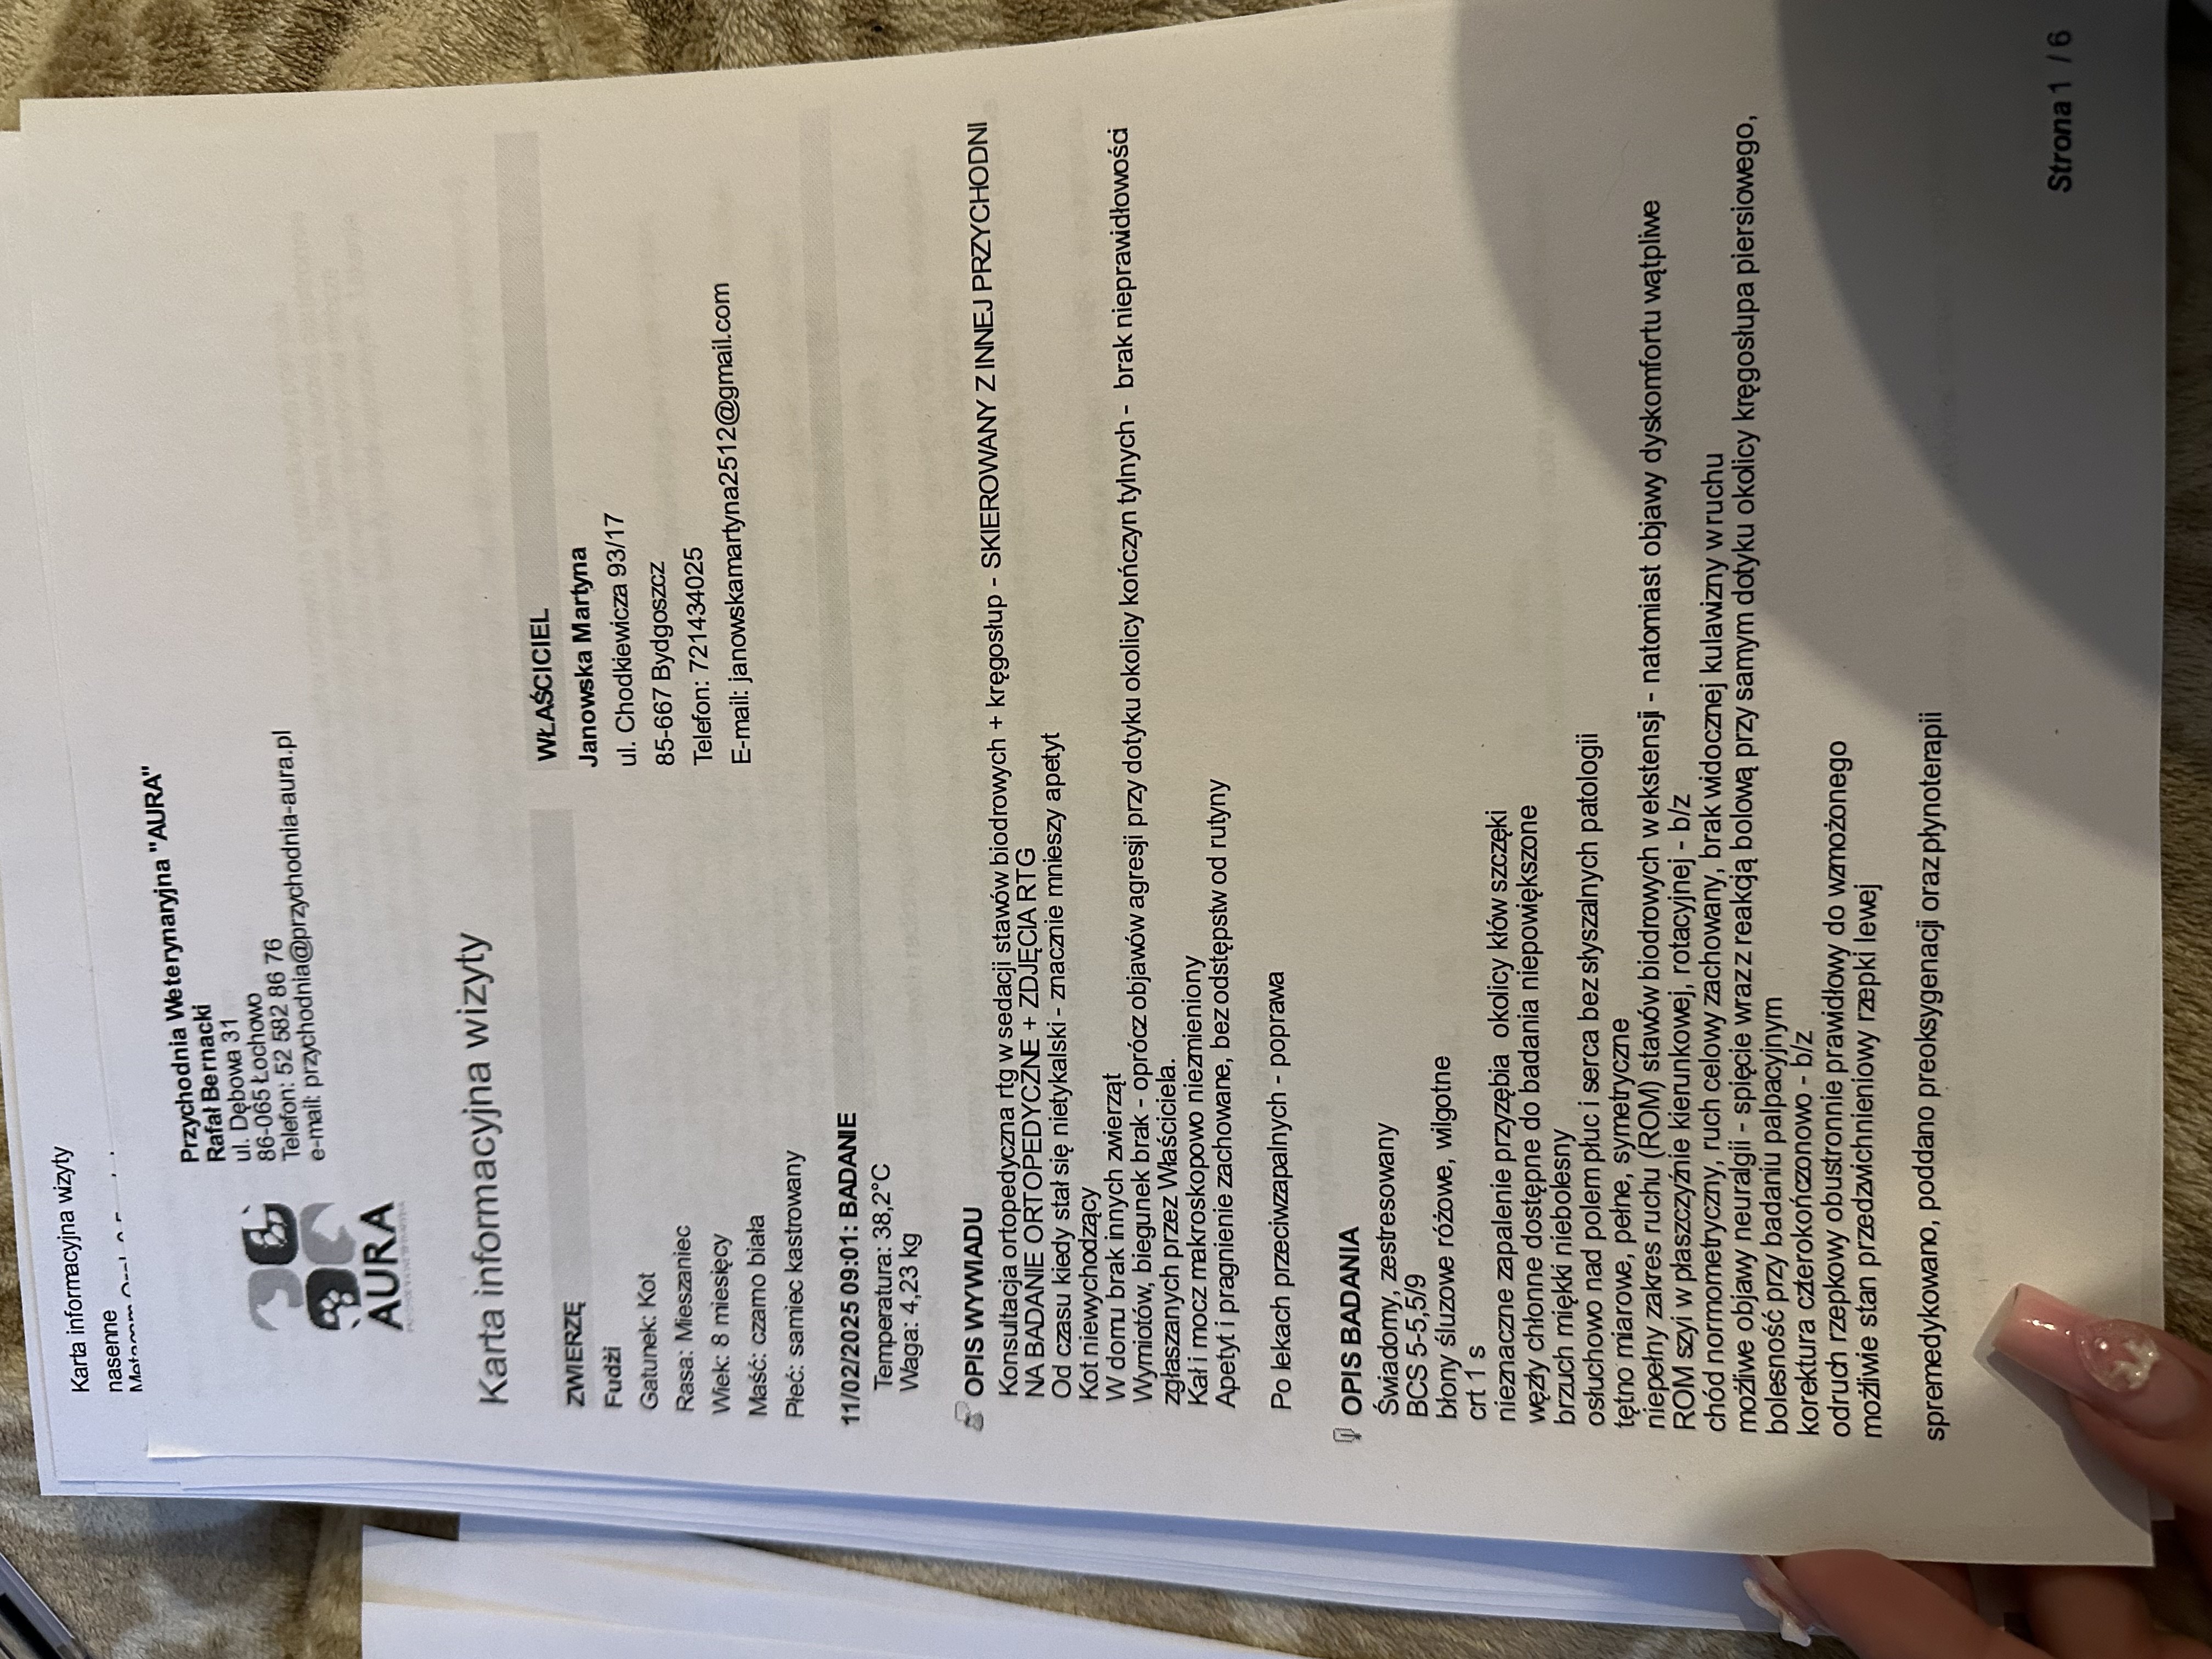

Pierwsza wizyta u weterynarza wykazała możliwe problemy ortopedyczne – Fudżi wykazywał silny stres, miał napięty grzbiet, a próba wyprostowania jego stawów biodrowych wywoływała agresję, co mogło świadczyć o bólu. Wstępnie podano mu leki przeciwbólowe (Loxicom, Rheumocam) i zalecono dalszą diagnostykę.

Kolejna konsultacja miała miejsce w innej klinice, gdzie lekarze nadal podejrzewali problemy ortopedyczne, dlatego przeszedł szczegółowe badania, w tym RTG kręgosłupa i bioder i konsultacje specjalistyczną. Wdrożono leczenie Gabapentyną oraz Metacamem, aby zmniejszyć ból i uspokoić kota. Zalecono dalszą obserwację oraz ewentualne kolejne badania, jeśli objawy nie ustąpią.

Kot wymagał dalszej diagnostyki – możliwe kolejne badania ortopedyczne (TK/MRI) oraz USG i biochemię z morfologią.

Pojawiło się podejrzenie Feline Hyperesthesia Syndrome (FHS) – zaburzenia neurologicznego, które może powodować nadwrażliwość skóry, niekontrolowane reakcje bólowe oraz zmiany w zachowaniu, a także zostało przeprowadzone badanie kliniczne i nie wykluczono problemów dermatologicznych w związku z agresywnym wydrapywaniem futerka (alergia, pasożyty). Zalecono obserwację i sprawdzenie reakcji na leki sterydowe.